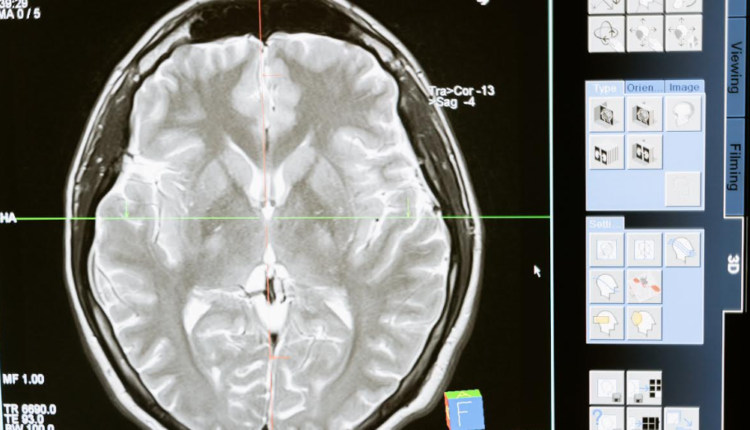

Ciudad de México, febrero de 2023.- Investigadores y colaboradores de Mayo Clinic han logrado hallazgos clínicos clave que pueden ayudar a los médicos a reconocer las causas que podrían tratar la demencia progresiva rápidamente en pacientes que, de lo contrario, podrían recibir un diagnóstico de enfermedad de Creutzfeldt-Jakob. Su estudio se publicó en la versión en línea de Neurology Clinical Practice, la revista médica oficial de la Academia Americana de Neurología.

De acuerdo con los investigadores de Mayo Clinic, son muchas las afecciones que pueden imitar a la enfermedad de Creutzfeldt-Jakob, con síntomas que incluyen cambios en la personalidad, pérdida de la memoria, convulsiones, dificultad en el habla o para tragar, y movimientos espasmódicos y repentinos. La enfermedad es rara, no tiene cura y tiene una supervivencia media de menos de un año. Diversas enfermedades neurodegenerativas, vasculares e inmunitarias presentan síntomas parecidos, y un pequeño grupo de pacientes puede recibir un diagnóstico equivocado de enfermedad de Creutzfeldt-Jakob. Después de presentar síntomas, muchos de estos pacientes se someten a pruebas para detectar la enfermedad de Creutzfeldt-Jakob en centros especializados y esperan días, o incluso semanas, hasta obtener los resultados.

Los investigadores utilizaron análisis estadísticos para revisar los resultados de pruebas de diagnóstico y características clínicas de pacientes que reunían los criterios de diagnóstico de la enfermedad de Creutzfeldt-Jakob, pero que, en última instancia, presentaban diferentes causas de demencia rápidamente progresiva. A continuación, compararon los historiales médicos de pacientes con aquellos de pacientes con enfermedad de Creutzfeldt-Jakob posible o probada. Los pacientes se habían evaluado en Mayo Clinic o en la Universidad de Washington en St. Louis entre 2014 y 2021.

Los pacientes que no tenían la enfermedad de Creutzfeldt-Jakob presentaban encefalitis autoinmunitaria, demencia frontotemporal, fístulas arteriovenosas durales, angiopatía amiloide cerebral, que puede derivar en un accidente cerebrovascular, o lupus sistémico. La mayoría tenía niveles elevados de glóbulos blancos que combaten la enfermedad o proteínas en el líquido cefalorraquídeo. Se detectaron anticuerpos en la sangre o en el líquido cefalorraquídeo de alguna de las afecciones a través de pruebas diagnósticas en los Laboratorios de Mayo Clinic.  En contraposición, se descubrió que la mayoría de los pacientes que de hecho tenían la enfermedad de Creutzfeldt-Jakob presentaban niveles normales de glóbulos blancos y proteínas en el líquido cefalorraquídeo.